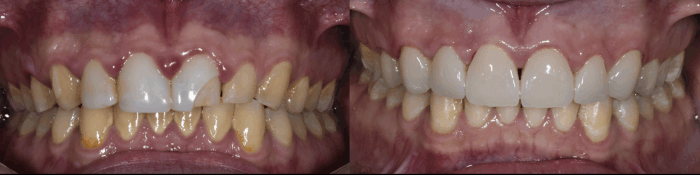

Descubre los increíbles resultados de nuestros tratamientos con esta galería de imágenes antes y después. En Bio Dental Clinic, combinamos experiencia, tecnología y atención personalizada para devolver la función, estética y confianza a cada sonrisa.